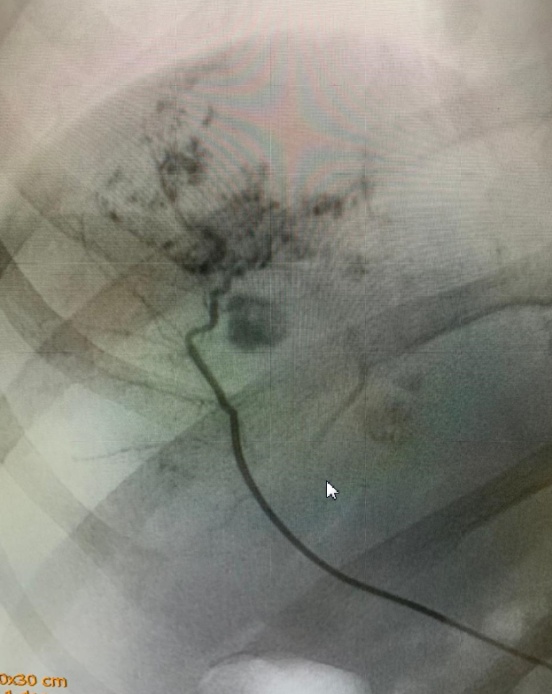

РЭО ветвей печеночной артерии выполнена 7 (11,86 %) больным с гемангиомами, расположенными интрапаренхиматозно в правой доле печени, и одному (1,7 %) пациенту с центральным расположением опухоли. Размеры опухолей достигали 10 см (рис. 4–5).

Рис. 4. Ангиографическая картина гемангиомы правой доли печени

Рис. 5. РЭО ветви правой печеночной артерии, кровоснабжающей гемангиому

Патогенетическим обоснованием для РЭО печеночной артерии послужило установление факта «патологического перераспределения артериального кровотока» при гемангиомах и других гиперваскулярных опухолях, кровоснабжение которых осуществляется в основном артериальной кровью. При этом возникает синдром «обкрадывания» непораженной печеночной паренхимы. В качестве эмболизирующего вещества применяли поливинилалкоголь, металлические спирали, микросферы, эмболы гидрогеля на основе полигидроксилэтилметакрилата диаметром 0,5–1,5 мм или другие препараты.